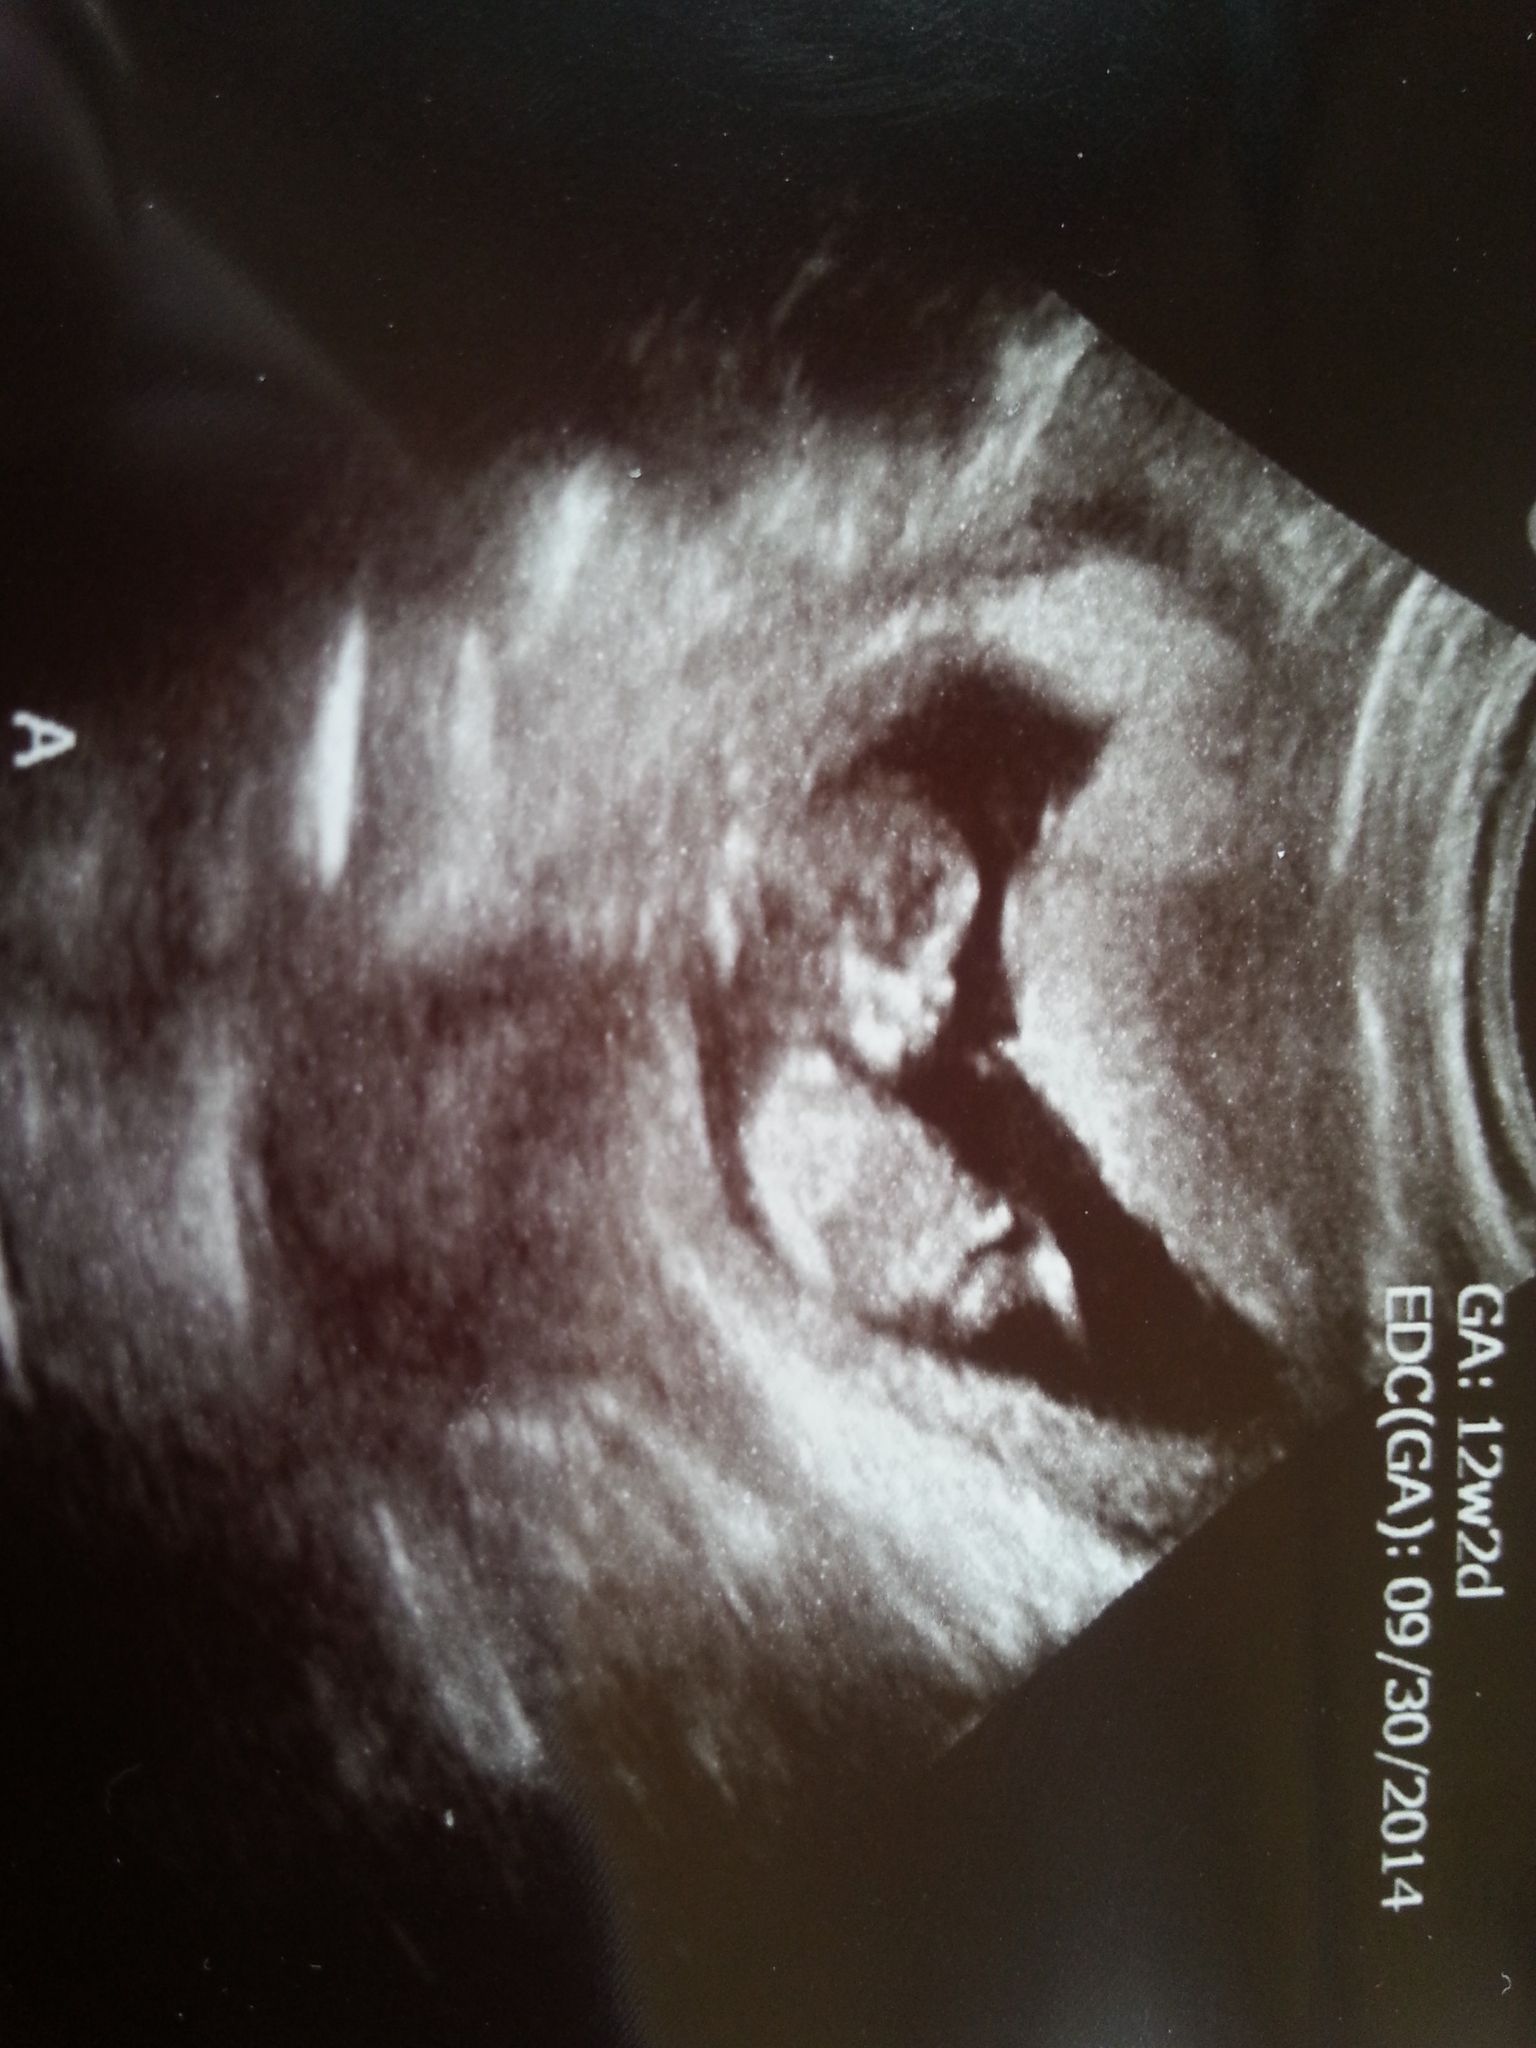

Attachment 18082Attachment 18083Attachment 18084Attachment 18085

We were in for the biggest shock to date when our 12 week, 2 day NT scan showed TWINS!!! We already have a 3 year old super sweet little boy, both of us are really hoping for a girl... but our tech thought boys??